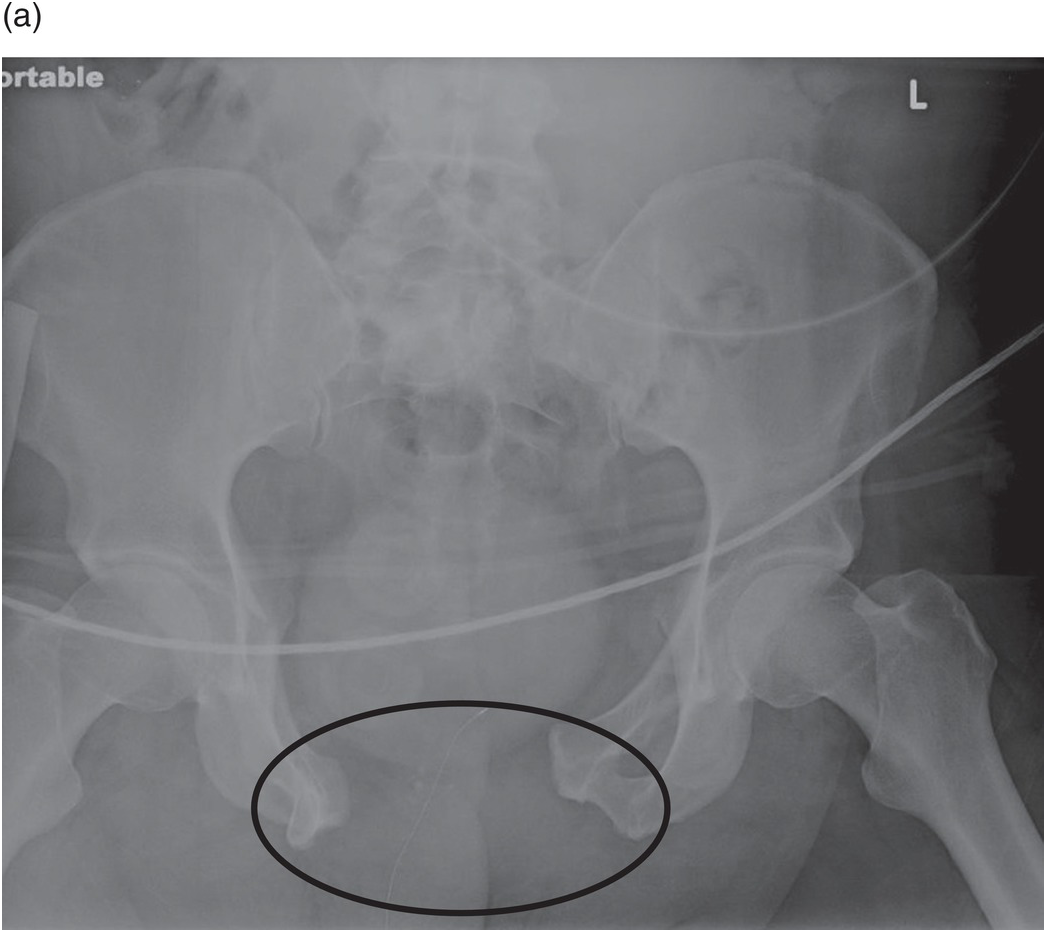

3 Pelvic Fracture Called Also Open Book Fracture In A 27 Year Old Male